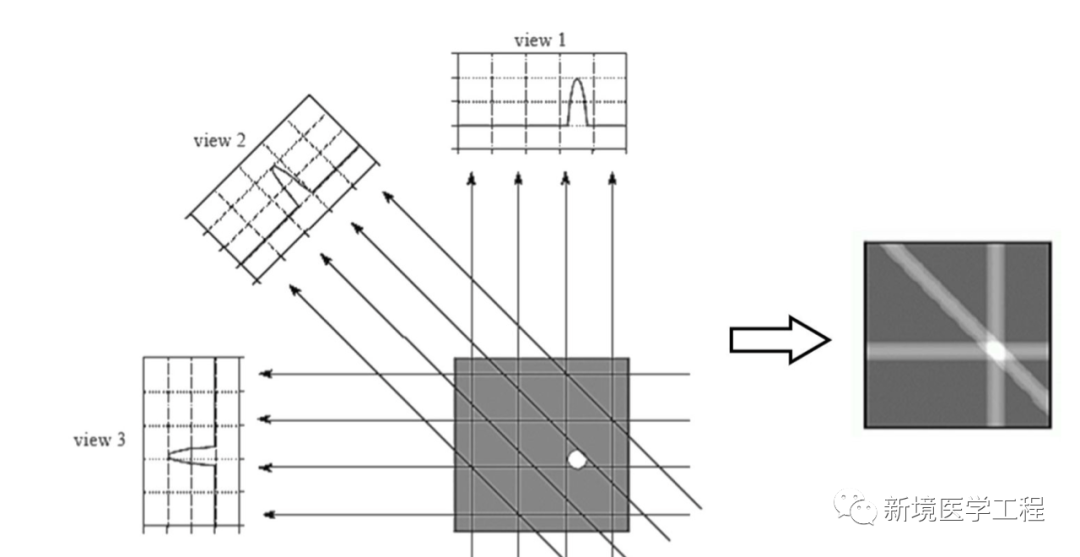

与常规X射线成像设备相比,CT系统本质上更容易产生伪影:一个CT图像是由大量投影生成的。在一个典型的CT系统中,每个投影包含大约1000个单独的测量,在多层CT的情形下,形成一幅图像需要使用10E19个独立信号读取或测量!由于反投影过程的本质是将投影中的一点映射到图像中一条直线(如下图),投影读数的一个误差不像常规射线照相的情况,不再局限于局部区域。因为测量的不准确通常表现为重建图像中的误差,所以CT产生伪影的概率明显偏高。